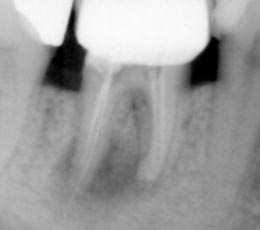

Επανάληψη ενδοδοντικής θεραπείας

Η επανάληψη μιας αποτυχημένης ενδοδοντικής θεραπείας θεωρείται ως η πιο περίπλοκη διαδικασία, που ενέχει αρκετούς κινδύνους για τη μελλοντική λειτουργικότητα του δοντιού. Η απόφαση για επανάληψη είναι συλλογική, μεταξύ της οδοντιάτρου και του ασθενούς, αφού συνεκτιμηθούν μια σειρά παραγόντων, με κυριότερους τη διάγνωση της αιτίας της αποτυχίας της προηγούμενης θεραπείας και το όφελος της επανάληψης.

Η επανάληψη μιας ενδοδοντικής θεραπείας δεν σημαίνει και τη διάσωση, τελικά, του δοντιού. Η δυναμικότητα των παθογόνων αναερόβιων μικροβίων που έχουν αναπτυχθεί στο σύστημα των ριζικών σωλήνων με τη συνεπακόλουθη καταστροφή των περιακρορριζικών ιστών καθιστά, πολλές φορές, αδύνατη τη διατήρηση του δοντιού, ακόμη και με το συνδυασμό της μικροχειρουργικής ενδοδοντίας.